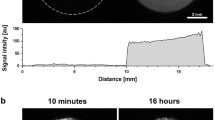

MR images from 200 μl injections of Gd-albumin are shown in Fig. 4. A comparison of the in vivo Gd-albumin images in Fig. 4 to the in vivo Gd-DTPA images in Fig. 1 for the 200 μl injection volume indicates that the concentration of Gd-albumin decreases more slowly with time compared to Gd-DTPA. This observation is further substantiated by the quantitative representation of mass clearance given in Fig. 5A (DTPA) and B (albumin). The average in vivo half-life of Gd-DTPA is 22 min and of Gd-albumin is 5.3 h, as presented in Table I. Figure 5A and B also show that the post mortem decline of Gd-albumin concentration is about four times slower than the post mortem decline of Gd-DTPA for the 200 μl injection experiments, as evidenced by the calculated half-lives which are given in Table I.